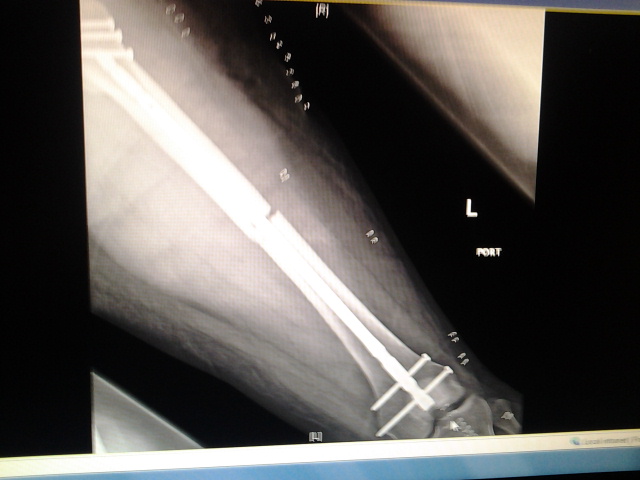

So... To start, I had a motorcycle accident and broke my leg in two places. They had to insert a rod and a bunch of screws in. But I think I had nerve damage. How I know? Well the outside of both my legs to the small toes are numb. Not totally, I have feeling. But they're numb.

I had the accident on 4-7-14. Been non-weight bearing on my left leg since.

Attachment:

2014-04-10 08.07.56.jpg

2014-04-10 08.07.56.jpg [ 91.21 KiB | Viewed 6295 times ]

Just don't ask me how my bike fared :/